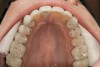

The signs of instability in the system would include wear that is beyond normal, tooth movement that is not wanted, broken teeth, and teeth with excessive mobility. The normal amount of wear for teeth is a slow process and follows a minimally progressive course. In an adult, tooth wear averages 10.7 µm per year. Exposed dentin is not normal and should be evaluated for the cause (Figure 1). Dentin wears at a rate far greater than enamel and this can cause wear and breakdown to accelerate.3 Tooth movement that is unwanted is the result of excessive forces on a tooth or breakdown of a tooth’s supporting structures. Normal teeth have 50 µm to 100 µm of mobility that varies by time of day and amount of forces applied. Numerous factors can lead to increased tooth mobility. Periodontal disease is a common cause of mobility; however, excessive load and lateral forces found in occlusal trauma can also cause this condition to exist.4 Thankfully, resolution of the mobility can resolve to pre-trauma levels once the cause is removed.5 Patients can exhibit varying degrees of some or all the signs of instability.

Figure 1  CENTRIC RELATION Exposed dentin such as seen in these incisors is not normal.

Figure 1